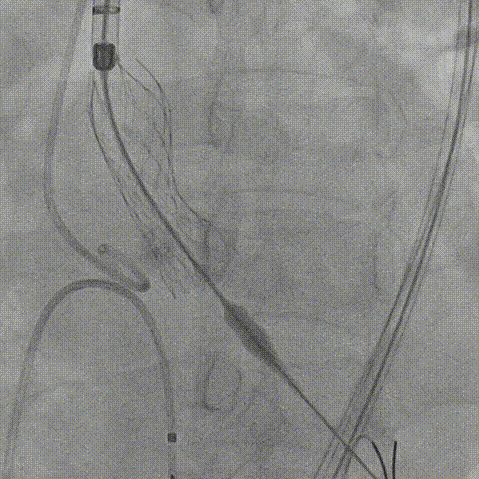

患者病史 主诉:发作性胸闷憋喘半年,加重伴呼吸困难2周。 现病史:患者半年前无明显诱因出现胸闷、憋喘,伴有下肢水肿,2周前上述症状明显加重,夜间不能平卧,痰中带血丝,为进一步诊治再次来我院,门诊以"心力衰竭"收入院。 既往史:肾功能不全、心房颤动 心脏超声提示:LVEF:0.54 1.主动脉瓣病变;2.主动脉瓣狭窄(重度)并反流(中度);3左室壁节段性运动不良;4.升主动脉扩张、双房扩大、左室肥厚;5.二尖瓣硬化并反流(中度);6.三尖瓣反流(轻-中度);7.肺动脉瓣反流;8.肺动脉高压(轻度)PGmean=105mmHg,Vmax=635cm/s,瓣口面积0.27cm²。 术前CT评估 Type0型二叶瓣,重度钙化,钙化集中在瓣叶游离缘,右冠窦为著;左冠高度11.8mm,由于左冠窦部空间较小,左冠风险较高, 升主动脉扩张,最宽处50.5mm;主动脉瓣环水平夹角61.5°,横位心。主动脉弓角77.6°,锐角弓,外周入路在腹主及髂总处有大量散状钙化,胸主处有81.6°的迂曲。 手术策略 推荐右侧股动脉为主入路,左侧股动脉为辅入路,送snare辅助过弯,使用18F大鞘,推荐预装ProStyle A® AV23瓣膜,20mm球囊预扩,初始定位对齐真实瓣环瓣上5mm超高位初始定位释放,释放过程中使瓣膜自然下滑,到工作位观察瓣膜形态,最终理想位置0-瓣下3mm。 手术过程 Step1:右侧股动脉为主入路、左侧股动脉为辅入路,成功穿刺并送入 18F 大鞘; Step2:主动脉根部造影,瓣口限制重 Step3:Type 0 型二叶瓣畸形合并重度钙化,患者瓣口狭窄严重,同时横位心,不仅导丝跨瓣困难,导管更难进入;术者凭借精湛操作,将导丝顺利跨瓣,反复微调导管角度,最终导管顺利过瓣。 导丝精准跨瓣 Step4:20mm球囊跨瓣困难,snare辅助下球囊成功跨瓣,预扩有腰无漏,冠脉充盈良好。 Step5: snare辅助下成功跨瓣,可以看到系统过弓形态瓣膜仓柔软,过弓顺滑 输送系统过弓 Step6:初始定位瓣上5mm开始释放,释放部分后观察瓣架下缘内收明显,后回收系统重新定位 初始定位 底部内收 Step7:瓣膜完全释放前,血压一度降低,术者迅速调整器械,实现瓣膜迅速锚定,快速释放 完全释放 Step8:20mm球囊后扩 最终造影,位置(瓣下3mm)形态良好 手术难点 患者不仅有主动脉瓣重度狭窄,还叠加肾功能不全、心房颤动等基础疾病,术中血流动力学波动极易引发心功能衰竭。ProStyle A® 预装干瓣“开包即用” 的特性压缩了术者操作时间,80%可回收设计给了术者容错空间,而这些看似难以逾越的难关,最终被团队精湛的医术一一化解,术中对于导丝、导管、球囊等器械每一步的精准操控,再到突发状况的从容处置,无不彰显着团队深厚的专业积淀与顶尖的操作技艺。 结语 此次手术的圆满成功,不仅彰显了陈玉国、李传保教授团队在复杂结构性心脏病介入治疗领域深厚的专业造诣与攻坚克难的决心,也充分验证了ProStyle A®系统在应对复杂高难度病例时的卓越适用性与有效性。 作为扎根齐鲁、享誉全国的医疗高地,山东大学齐鲁医院始终赓续着这片热土的仁厚文脉,将“医道从德,术业求精”的院训精神镌刻在每一次诊疗实践之中。特别是在结构性心脏病诊疗领域,医院团队始终怀揣医者担当,勇攀医学高峰,不断以更前沿的技术突破,为危重患者点亮重获新生的希望。 专家简介 陈玉国 山东大学齐鲁医院(点击查看专家详细简历) 李传保 山东大学齐鲁医院(点击查看专家详细简历) · END ·

最终造影